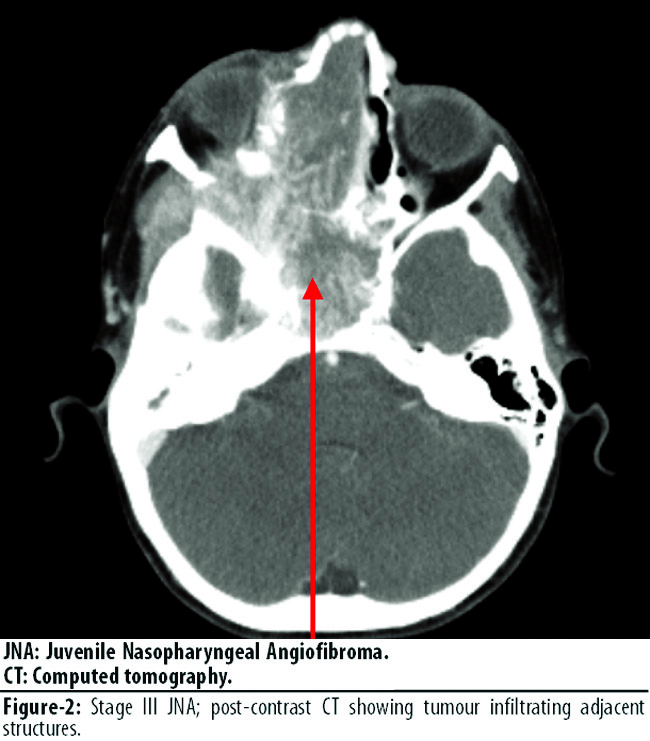

5 (27.77%) patients as stage II, 4 (22.22%) patients as stage IIIa (Figure-2),

1 (5.55%) as stage IIIb, and 4 (22.22%) patients as stage IVb. Tumours with a higher stage presented at an earlier age (Table-1).